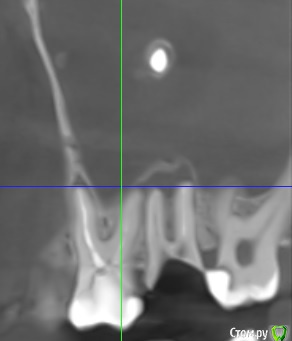

b.yakimenko Опубликовано 18 ноября, 2015 Поделиться Опубликовано 18 ноября, 2015 Добрый день. Все началось из того что год назад после простуды я начал чувствовать запах гноя в носу. Записался к лору, сказал что это из за разрушенного зуба, верхней семерки, и посоветовал мне сходит к ЧЛХ, хирург сразу направил сделать КТ, после просмотра снимка выявилось что в гайморовой пазухе инородное тело(больше всего что пломбировочная масса) в итоге предложил удалить 7 и 6 зуб и сделать гайморотомию. Позже выяснилось что операцию можно провести эндоскопом.Прошу вашего совета как мне начать процедуру лечения, и что можете сказать по этим зубам? Прилагаю снимки КТ 6 и 7 зуба и гайморовых пазухДо лечени 6 заба https://drive.google.com/open?id=0B5ho3pIiCaXYQVE0emVQVUJoNzQПосле лечения https://drive.google.com/file/d/0B5ho3pIiCaXYci0tRW1fUV9hQ3c/view?usp=sharing Ссылка на комментарий

b.yakimenko Опубликовано 19 ноября, 2015 Автор Поделиться Опубликовано 19 ноября, 2015 Пока не удается открыть КТ.Из ваших слов непонятно зачем, как и когда лечили 6 зубхирург сказал что шестой зуб идет на удаление, потому что не все каналы свое время были пролечены и там осталось воспаление, попасть в те каналы особо трудно, и делать операцию не устранив воспаления будет неправильно. три месяца назад стоматолог попытался пройти в незалеченые каналы, в некоторые он прошел, но при повторном КТ воспаления осталось. От 7 зуба остался пенек, врачь сказал что он разрушен кариесом.По поводу КТ, я выложил заархивированную папку 3D снимка, делал снимок в http://www.planmeca.com/ru Ссылка на комментарий

kozloff Опубликовано 19 ноября, 2015 Поделиться Опубликовано 19 ноября, 2015 (изменено) 6 и 7 удаление. Может быть и 8 тоже?И к ЛОРу на операцию. Изменено 19 ноября, 2015 пользователем kozloff Ссылка на комментарий